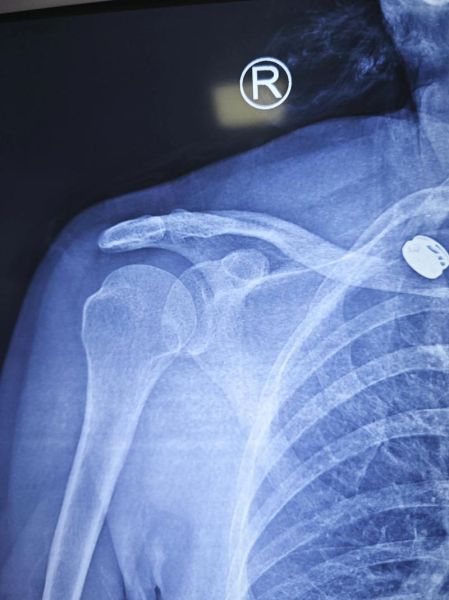

宝宝肩膀脱臼,医学上称为“肩关节脱位”或“桡骨头半脱位”,在婴幼儿阶段并不罕见。很多家长第一次遇到时都会惊慌失措:孩子突然大哭、手臂垂着不动,却又看不到明显外伤。到底哪些表现提示肩膀脱臼?家长在家能做哪些初步判断?以下内容用问答+分块的方式,一次性讲透。

(图片来源网络,侵删)